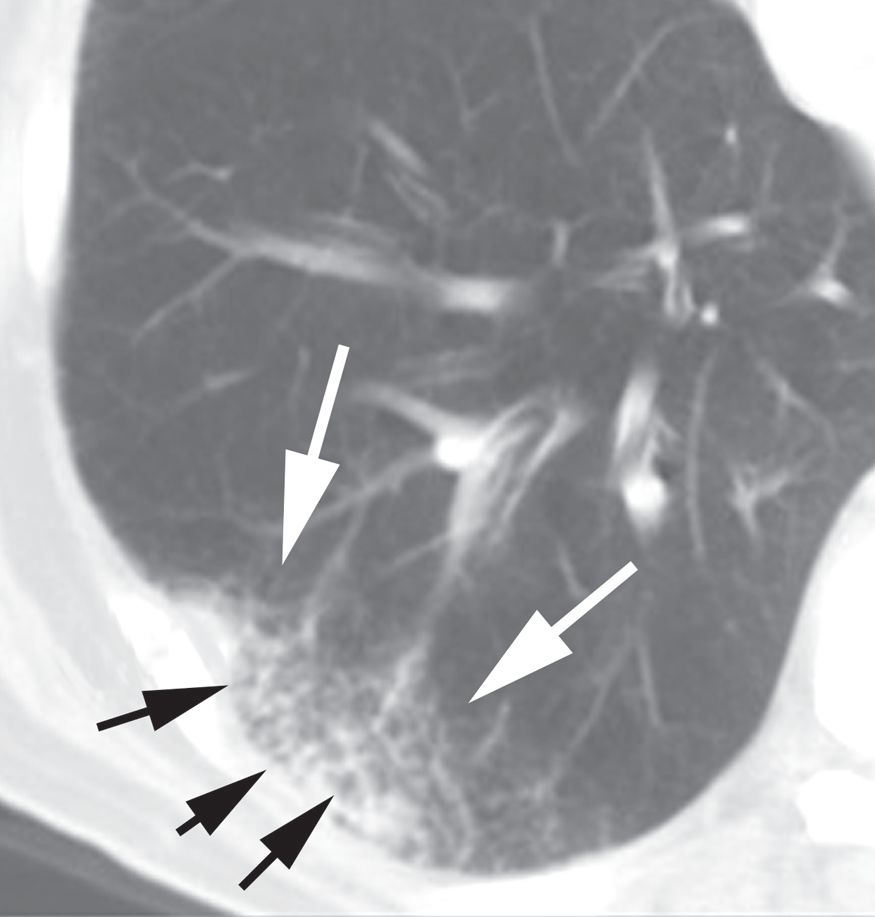

图2-4 实变,斑片状致密影

A、B. 支气管肺炎及小叶性实变患者增强HRCT显示单个小叶实变而周围邻近小叶正常,实变区小叶中心动脉( 白箭头) 和细支气管( 黑箭头);C. 冠状面CT 也显示斑片状实变影呈小叶性分布

斑片状肺实变有时在胸部X线片或CT 上显示为小叶或多小叶的病变( 包括孤立的肺小叶)( 图2-4),可表现为一些小叶密度增高而邻近小叶充气正常。